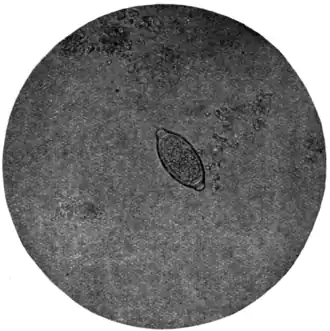

Ova of Trichiuris trichiura (Fig. 168, c).—Of the three common nematodes mentioned—Trichiuris trichiura, Ascaris lumbricoides, and Ankylostomum duodenale—the ova of the first are the most frequently met with. They occur sometimes in enormous numbers, as many as six or eight specimens being visible in one field of an inch objective. They form a rather striking object under the microscope (Fig. 170). They are oval, measuring 51 to 54 μ by 21 to 23 μ, the ends of the long axis of the oval being slightly pointed and tipped with a little shining projection or plug. Their general appearance suggests an elongated oval tray, the projections at the poles of the ovum representing the handles of the tray. They are dark brown in colour, sharply defined, doubly outlined, and contain no differentiated embryo.

Fig. 170.—Ovum of Trichiuris trichiura, x 280. (Photograph by Dr. J. Bell.)